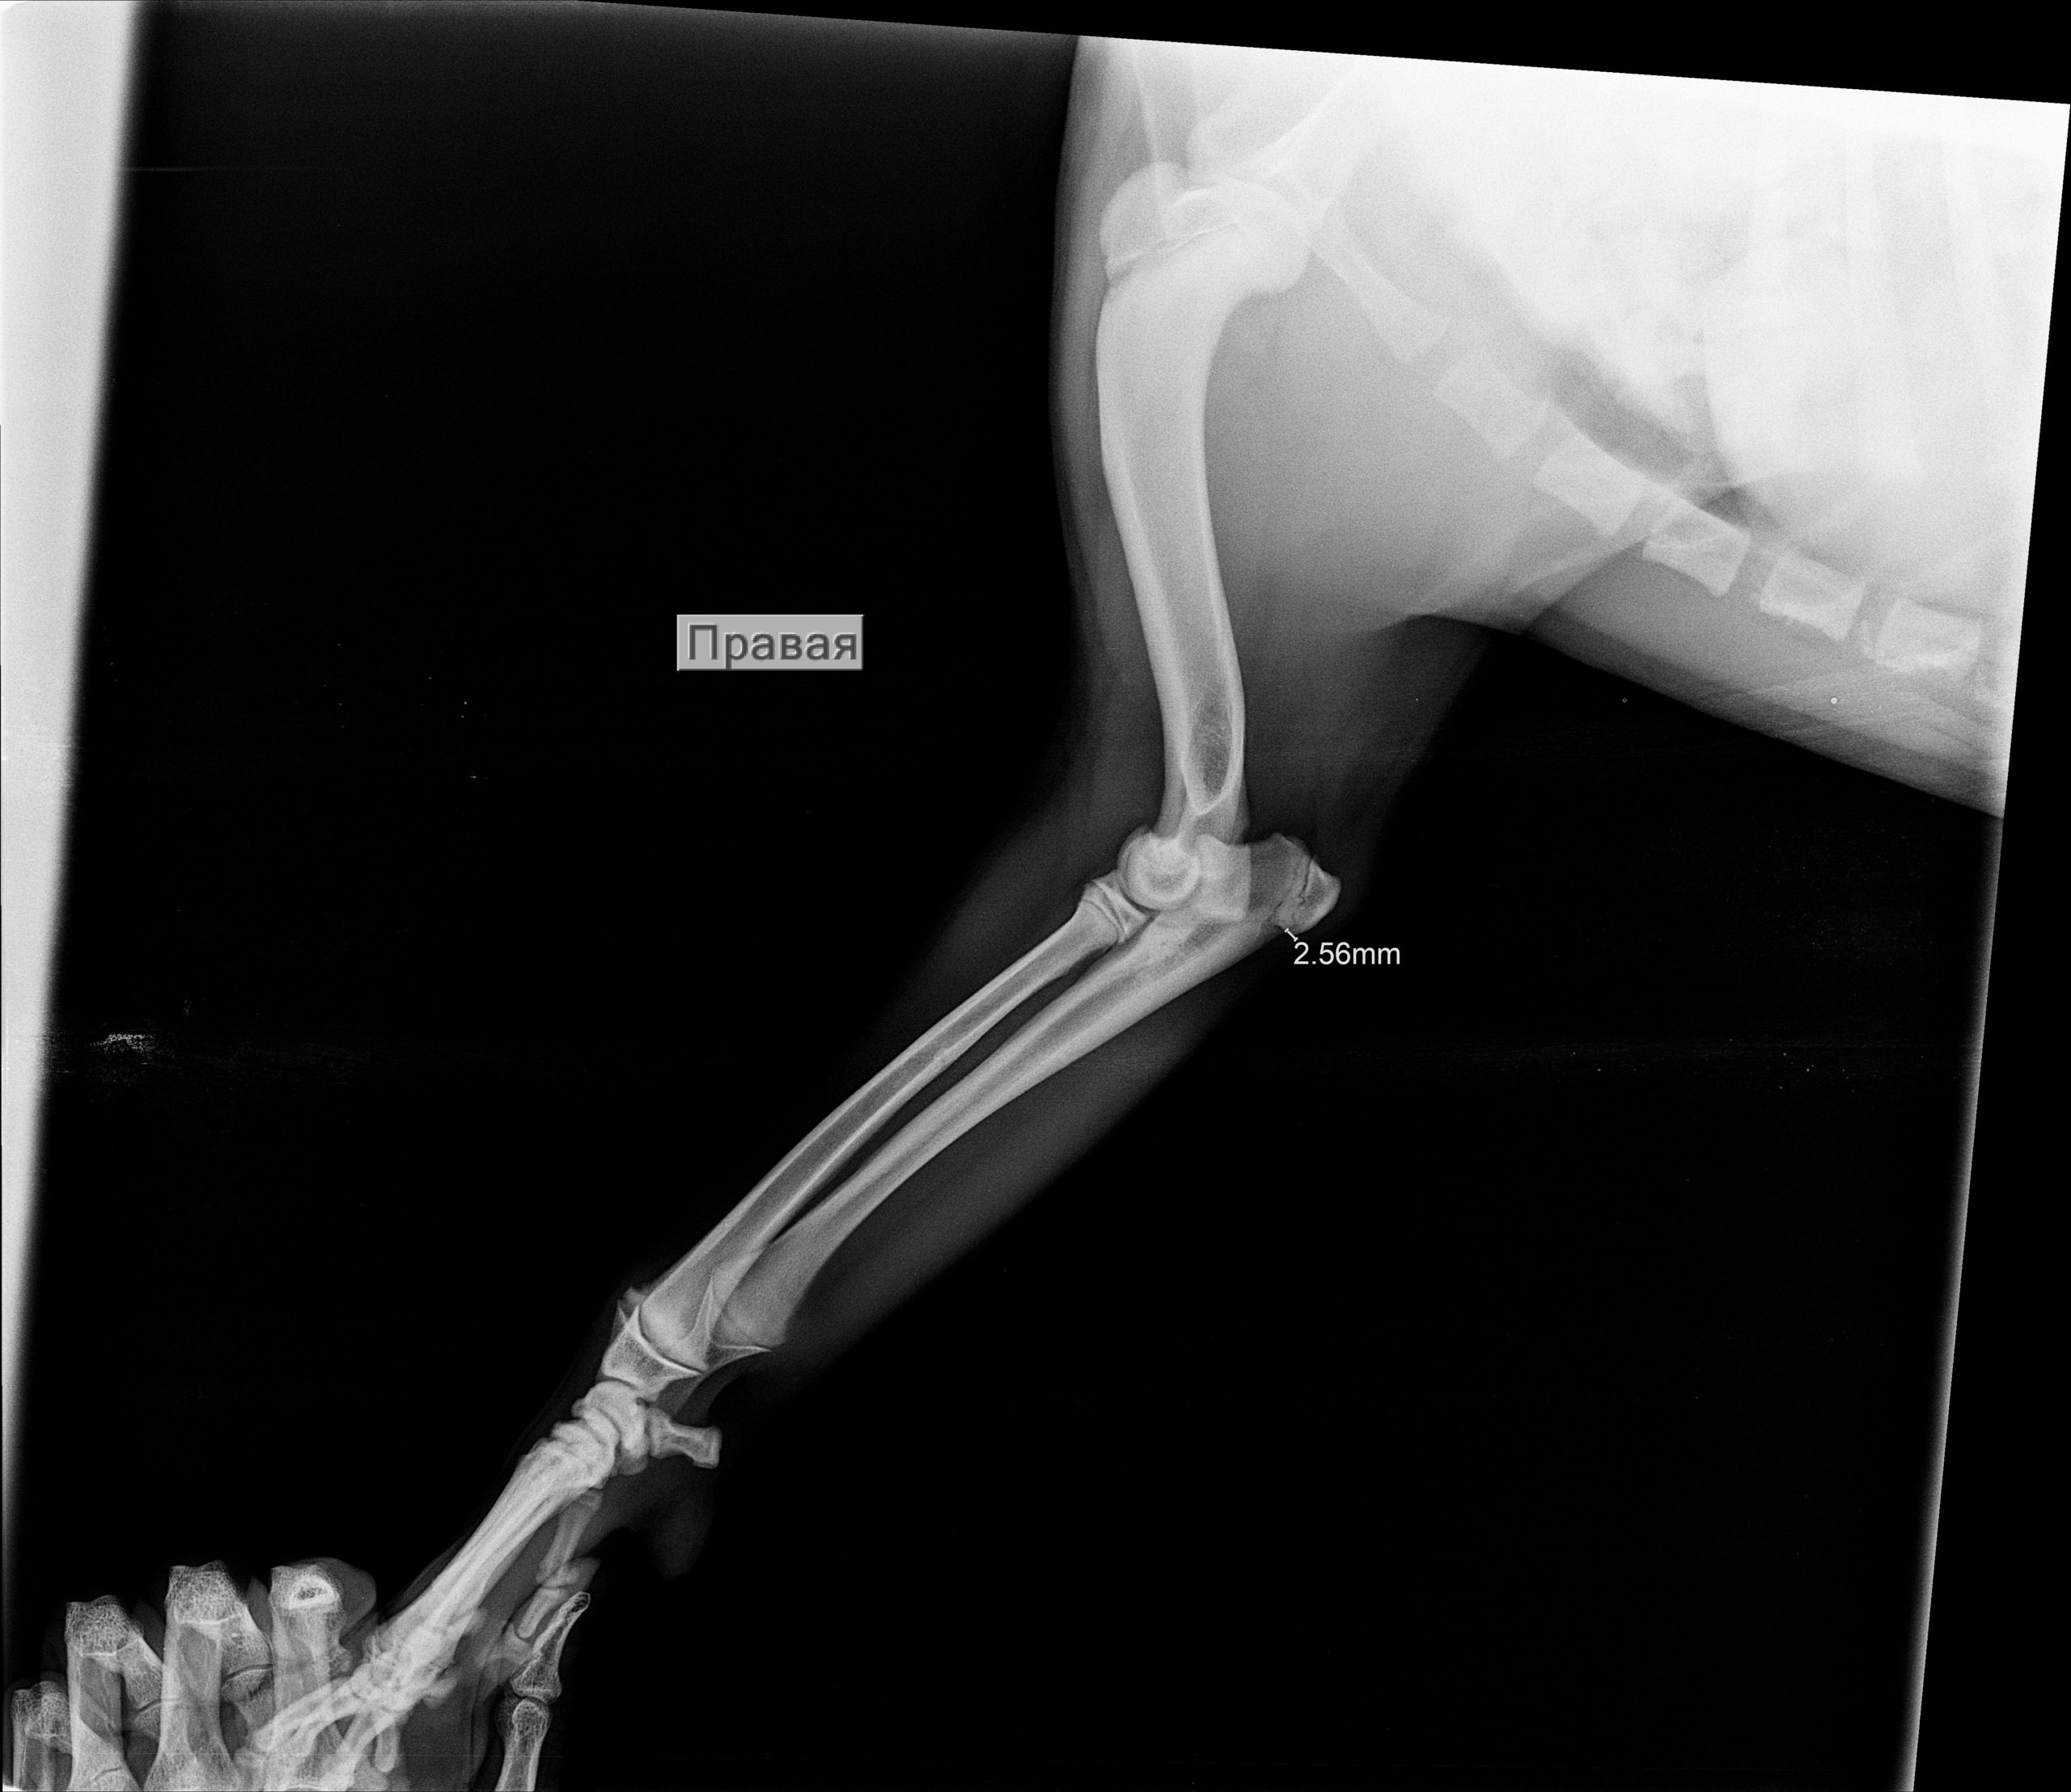

Рентгеновские снимки перелома лапы у кота: диагностика и лечение